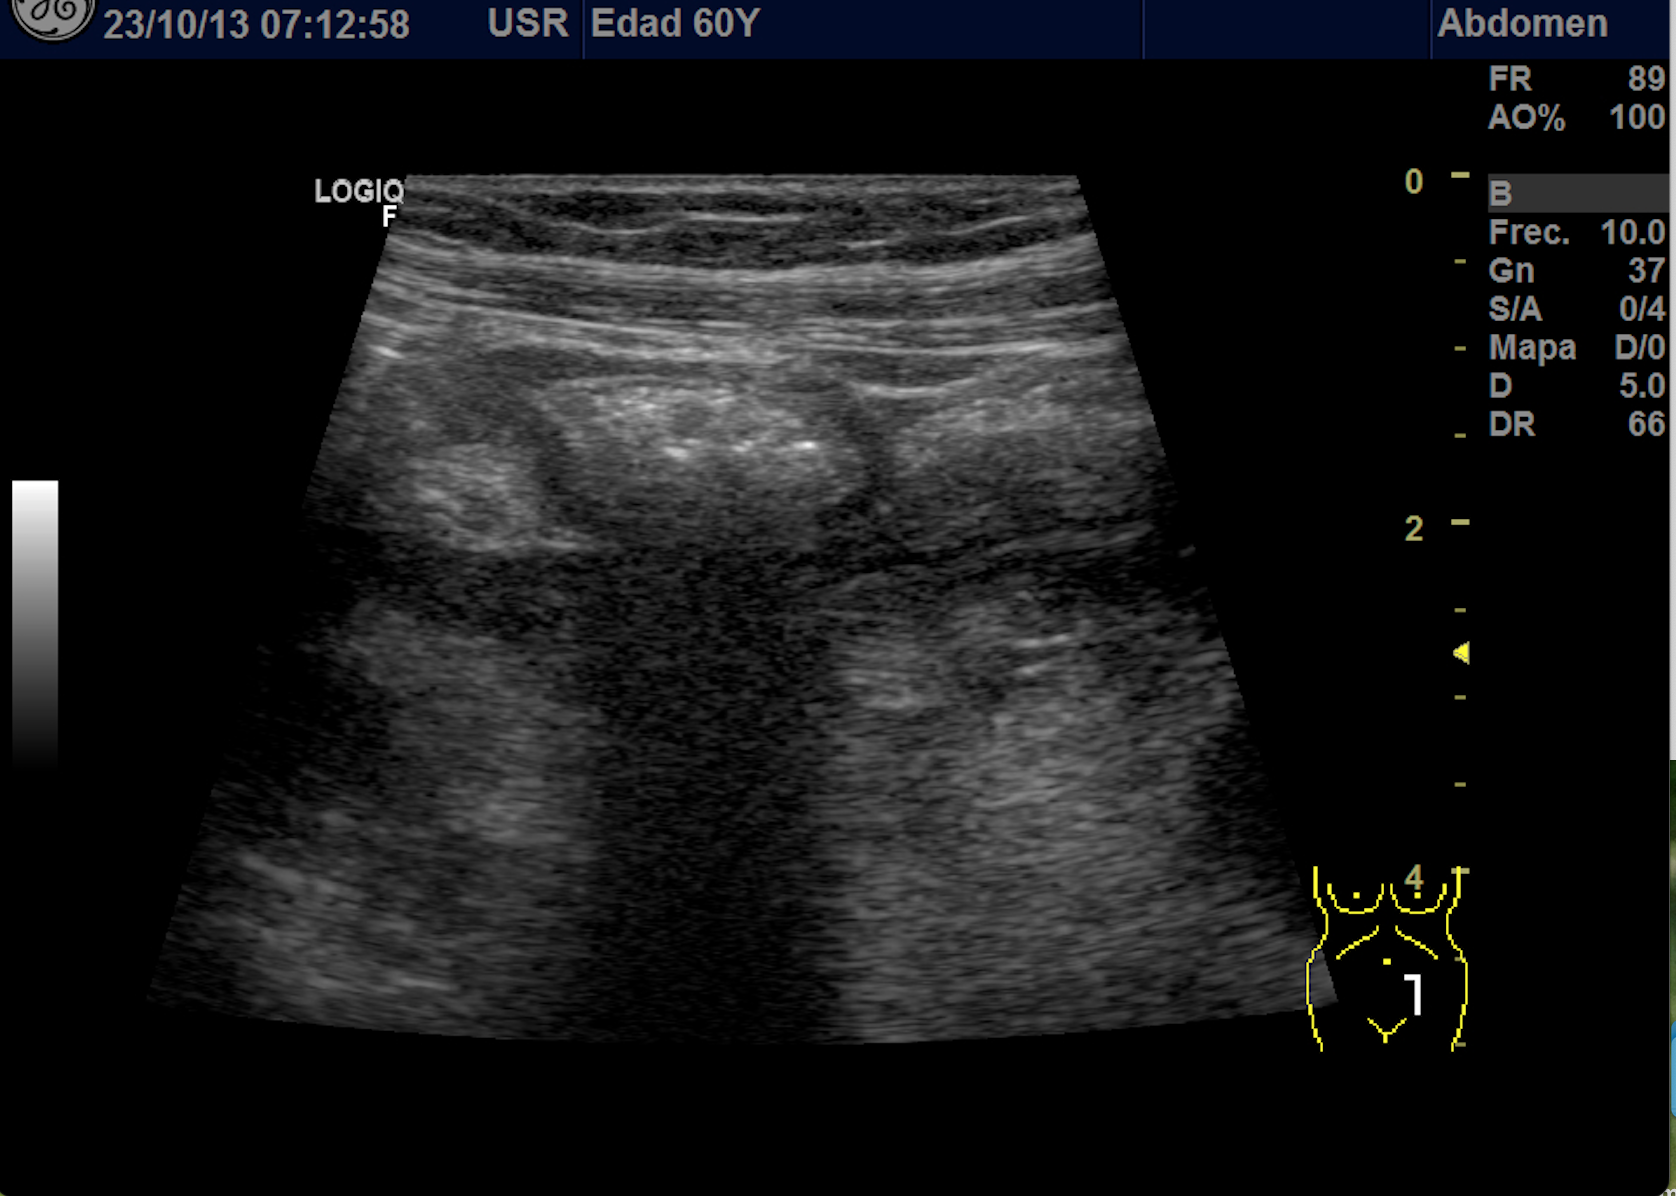

Se explora FII-hipogastrio y en el punto de más dolor se observa engrosamiento de asas de intestino grueso sin peristaltismo y con signos de edema de la grasa adyacente. No líquido libre.

También se realiza ecografia en urgencias del hospital.

En el hospital se realiza una nueva ecografía en el servicio de radiología confirmando el diagnóstico de sospecha: diverticulitis aguda en sigma distal sin datos de complicación. Hinchey 1A.